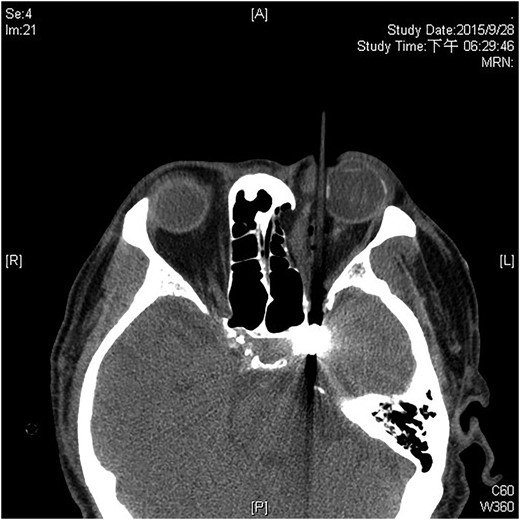

A 60-year-old man was admitted to our medical ward due to aspiration pneumonia. He had a medical history of diabetes mellitus, end-stage renal disease; a tuberculosis bacilli-related thoracic spine infection with paraplegia, and a previous coronary artery bypass graft. During his third day at the hospital, he obtained a ballpoint pen and inserted it into his left eye. On physical examination, the patient appeared to be alert with normal vital signs. The ballpoint pen protruded from his left upper eyelid; it was firmly lodged in his left medial orbit between the globe and nose, causing left eye proptosis (Fig. 1). Neurologic examinations revealed that the patient was neurologically intact except for complete left ophthalmoplegia. Brain CT scanning revealed a tubular foreign body that was located in the anteroposterior plane extending from the orbital apex and directly into the parasellar region (Fig. 2). The metallic portion of the foreign body was entrapped in left optic canal (Fig. 3). There was no evidence of intracranial hemorrhaging or a rupture in the globe (Fig. 4). The patient was treated with high-dose steroids to protect the optic nerve. The plastic ballpoint pen and metallic tip was withdrawn from the orbit smoothly at bedside, and no craniotomy was required. The ballpoint pen had been inserted to an estimated depth of 7 cm through the eyelid and into the orbit. The patient was then transferred to the ICU for close neuro-observation. We initiated intravenous broad-spectrum antimicrobials and vancomycin therapy and continued these medications for three weeks. A psychiatrist was consulted for a complete psychiatric evaluation and suicide prevention. The follow-up CT scan showed no retained foreign bodies or intracranial hemorrhaging (Fig. 5). At the last follow-up examination 2 months after the injury, the patient presented with complete left ophthalmoplegia and blepharoptosis but intact visual function.

The follow-up CT scan shows residual hematoma in the orbital cavity; no retained foreign bodies or intracranial hemorrhaging.